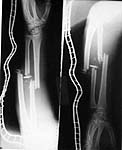

I did a debridement and could get a satisfactory field for internal stabilisation. The options I had kept were Ex fix, antegrade nailing and retrograde nailing. Had to be prepared for an arterial exploration if required. The vascular bundle was lying exposed through the compounding wound and could get the pulse beyond the fracture site. For this purpose I used a radioluscent flat table and did not use traction table intra-op.

After debridement I did a retrograde nailing using a solid SIGN nail. I thought this gave me the best chance to do with minimal disturbance to the head end on a flat table where the patient was supine. Sepsis to the knee was a worry but since I was using a solid nail I was fairly confident that the two area of concern( the fracture site and knee joint) will be sparated and will not spread infection from one place to other.

Post op patient is doing well but for mildly raised cpk secondary to muscle damage. This is settling.

You will find attached the final follow up picture:

halo

I was disappointed that there was not even one comment after the cervical spine dynamic views were presented. Though there is instability, the CT picture showed that the body of C2 was totally comminuted and hence a decision to keep the patient in Halo was taken by my colleague in charge of the spine unit. After the consolidation of the body of C2 if required he will go through a formal C2-3 fusion.

What would have been the fate of this patient in this part of the world if we did not have the facility to do intramedullary nailing and CT assessment? Can we imagine this patient being kept on tibial and skull traction for over six weeks?? Definitely this will not be suitable for an citizen of first world. But I feel even for the third world citizens this treatment we gave cannot be termed a luxury.

You will find attached in the remaining pictures the story of a young adult involved in a road traffic accident referred to us in shock. He had a major abdominal injury and had almost arrested before we took him up for surgery. After the abdomen was done I could boldly do the extremities thanks to the availability of nailing instruments and ventilator in the ICU. Of course he went through a rough period of rhabdomyolysis and an intensive critical care with daily battery of investigations which included electrolyte assessment, haemogram, blood gases, renal parmeters etc. Well yesterday I could shift him out of the ICU. Was his life and limbs saved through luxury of Western technology ?? I think it is only the availability of modern technology which has made us save these patients. Of course I envy the operation theatre I see in the Animal planet Channel. But with the limited infrastructure and not so high tech ICUs we can still save limbs and lives.